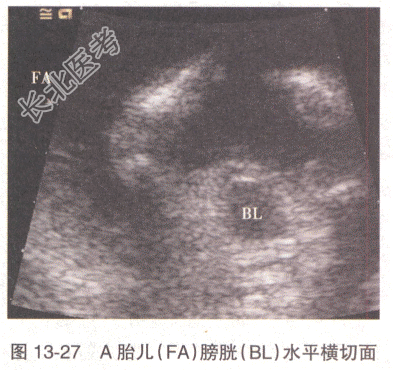

患者,女性,31岁。孕2产0,孕22周,感觉腹胀1周。无阴道流血及流水史。孕12周时超声检查示宫内妊娠,单绒毛膜囊双羊膜囊双活胎,A胎儿NT0.32cm,B胎儿NT0.12cm。22周超声检查,双胎儿解剖结构均未见明显异常,其余超声见图13-24~图13-27。

A、A胎儿为受血儿,膀胱明显增大

C、A胎儿为受血儿,羊水过多